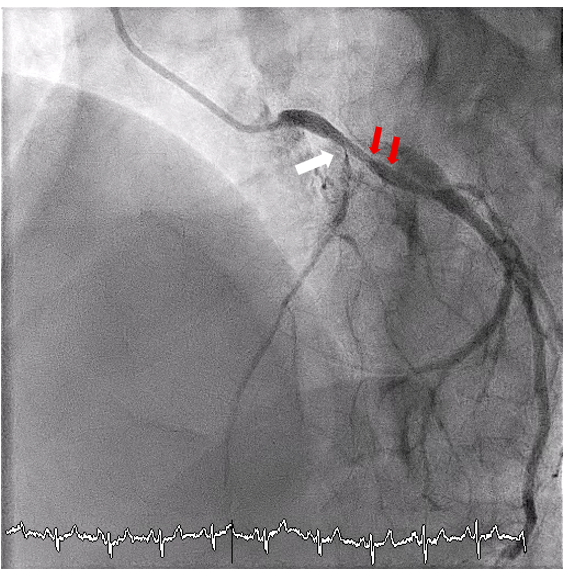

Real-time intravascular ultrasound (IVUS)-guided wiring of the LAD was then planned. An AltaView IVUS catheter (Terumo) was placed at the LCx wire. The IVUS lens served as a landmark for the ostial LAD. A Gaia Next 1 wire (ASAHI INTECC) supported by a single-lumen HighTrack microcatheter (Terumo) was then used to wire the ostial LAD (Figure 2). The Gaia Next 1 wire successfully crossed the ostial LAD lesion, as confirmed by IVUS (Figure 3). It was subsequently exchanged for a Gaia Next 2 (ASAHI INTECC) wire through the microcatheter to address another tight lesion in the proximal LAD. The procedure was completed successfully following balloon dilatation and stenting (Figure 4). The total amount of contrast use was 35 mL.